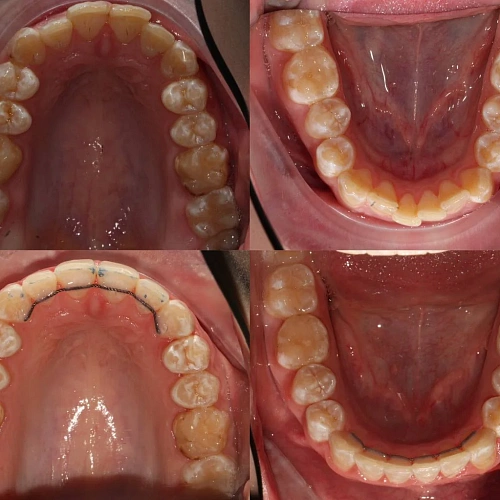

Нарушение соотношения челюстей и неправильное положение зубов — зубные ряды смыкались некорректно, зубы стояли со смещением.

Проблема: Пациентку не устраивало положение зубов и то, как смыкаются челюсти. Зубы стояли неровно, ряды сходились неправильно.